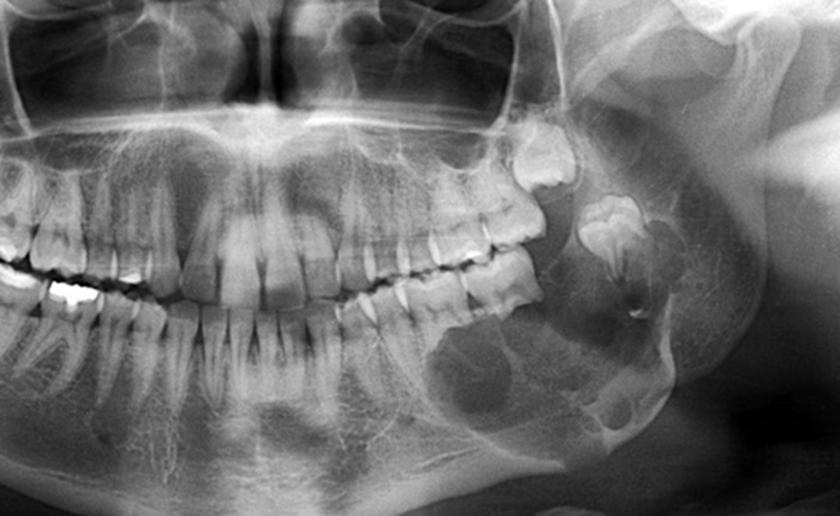

Hình ảnh của Kasim Hoàng Vũ khi mắc bệnh nặng, gương mặt biến dạng khó nhận ra

U xương hàm là tình trạng xuất hiện khối u phát triển bất thường trong xương hàm trên hoặc hàm dưới, có thể là u lành tính hoặc ác tính. Bệnh không phổ biến như sâu răng hay viêm nha chu nhưng lại âm thầm và dễ bị bỏ qua vì triệu chứng ban đầu khá mờ nhạt.

Tác động của u xương hàm lên sức khỏe không chỉ dừng ở vấn đề thẩm mỹ. Khi khối u phát triển, người bệnh có thể thấy sưng nề vùng má hoặc lợi, đau âm ỉ, tê môi cằm, răng lung lay không rõ nguyên nhân, khó nhai hoặc há miệng hạn chế.

Nếu là u ác tính, khối u có xu hướng xâm lấn nhanh, phá hủy cấu trúc xương, lan vào xoang hàm, hốc mắt hoặc nền sọ. Điều này có thể gây biến dạng khuôn mặt, suy giảm chức năng ăn nhai, nói chuyện và ảnh hưởng nghiêm trọng đến tâm lý người bệnh.

Biến chứng nguy hiểm nhất là nhiễm trùng lan rộng, gãy xương hàm bệnh lý do xương bị phá hủy, và đặc biệt là di căn xa nếu khối u mang tính chất ung thư. Ung thư xương hàm có thể lan tới phổi, gan hoặc hạch bạch huyết. Khi bệnh được phát hiện muộn, việc điều trị trở nên phức tạp, phải kết hợp phẫu thuật cắt bỏ rộng, xạ trị hoặc hóa trị.